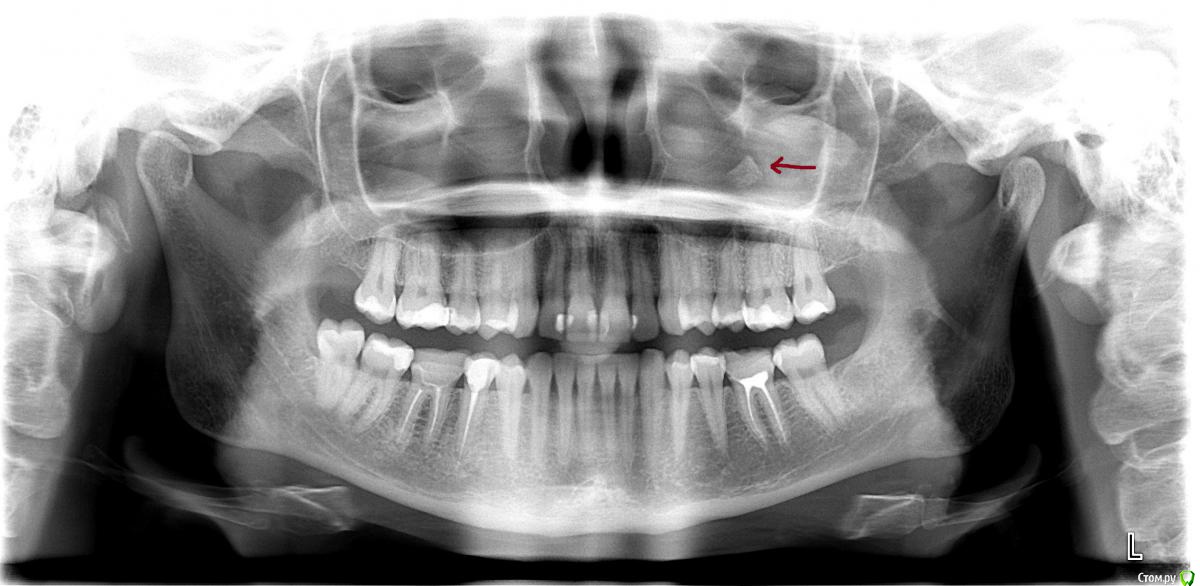

Viktoryaa Опубликовано 25 ноября, 2015 Поделиться Опубликовано 25 ноября, 2015 (изменено) Здравствуйте! В течении года стали появлятся неоднократно синуситы,сделали компьютерную томографию и лор сказала ,что со стороны лор-органов все впорядке.На томограмме она увидела какое то образование со стороны зубов верхней челюсти слева,посоветовала обратиться к стоматологу для дальнейшего исследования. К стоматологу записалась только на 18 декабря,а сегодня не выдержала и сделала панорамный снимок зубов.Не могли бы вы прокоментировать этот снимок? Красной стрелкой указала непонятноe образование.Так же хочу добавить,что 2 года назад мне перелечивали зубы слева на верхней челюсти.У 6 зуба под старой пломбой был обнаружен глубокий кариес,зуб не депульпировали,а поставили лечебную прокладку и запломбировали.Зуб беспокоил только первые 6 месяцев после перелечивания(реагировал на холодное и горячее).Врач сказал ,что этот срок нормальный ,так как кариес был глубокий.Больше зуб не беспокоит.Так же в прошлом году делала снимок всех зубов и на снимке никакого образования не было. Изменено 25 ноября, 2015 пользователем Viktoryaa Ссылка на комментарий

Viktoryaa Опубликовано 26 ноября, 2015 Автор Поделиться Опубликовано 26 ноября, 2015 Вот еще прикрепляю снимок 2014 года-в пазухе ничего нет.В носу на снимке это сережка Ссылка на комментарий